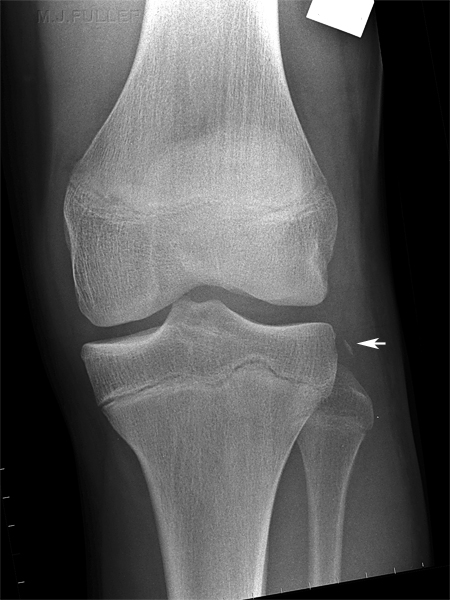

Segond Fracture

This is a very subtle "avulsion fracture of the tibia below the articular margin" caused by traction on the capsular or coronary ligaments. It is not possible to cause this fracture without first rupturing at least one of the major ligaments in the knee.

Examples in order of increasing subtlety: -